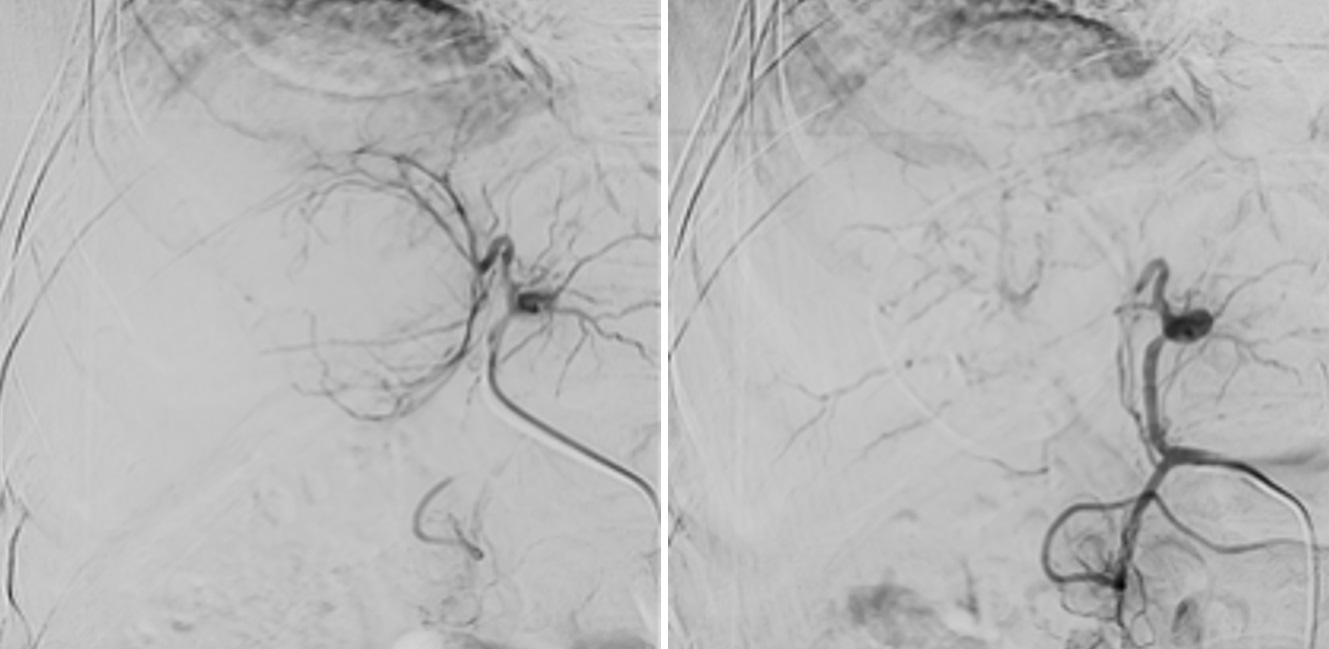

Introducción: La quimioembolización transarterial (QETA) es el tratamiento de elección para el hepatocarcinoma (HCC) estadio intermedio; sin embargo, estudios recientes reportan similares tasas de respuesta, sobrevida y menores reacciones adversas con embolización blanda (EB). Objetivo: Comparar eficacia, sobrevida y seguridad de QETA y EB para el tratamiento de HCC. Métodos: Estudio observacional retrospectivo de pacientes tratados mediante QETA o EB para HCC en el Hospital de Puerto Montt entre 2018 y 2025. Se realizó un control con resonancia magnética a las 6 semanas. Resultados: Se incluyeron 28 pacientes (15 hombres), de edad promedio 69 años, con daño hepático principalmente de etiología metabólica. Se realizaron 19 QETA y 15 EB, con 5 complicaciones leves (4 en QETA) y 2 fatales (1 QETA y 1 EB). Ambos métodos lograron similar tasa de respuesta favorable (63% vs 71%); sin embargo, QETA logró mejor tasa de respuesta completa (9 (50%) vs 1 (7%)) y mayor sobrevida (27 vs 23 meses). No se identificó asociación entre Child-Pugh, etiología ni sexo con desenlaces clínicos-radiológicos. La presencia de una única lesión se asoció a mejor respuesta, mientras que no haber logrado un 100% de avascularización en el procedimiento se asoció a peor respuesta. Conclusiones: QETA continúa siendo una opción terapéutica preferente, con tendencia a mejor respuesta tumoral y sobrevida respecto a EB, aunque más costosa y con mayor riesgo de complicaciones, por lo que EB aún debe considerarse como una alternativa, especialmente en pacientes frágiles o centros con menor presupuesto.